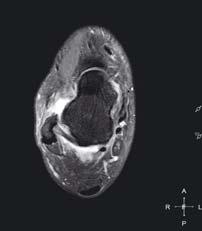

zwyrodnieniowa stawu skokowo-goleniowego

Staw skokowy dolny